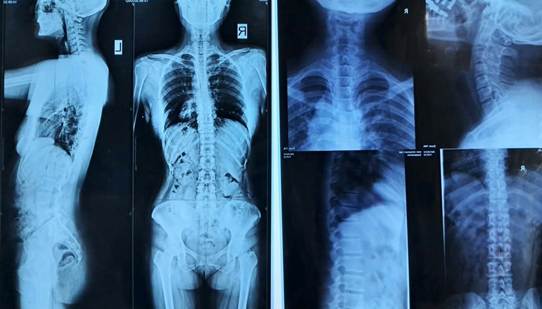

Хэрэв сколиозтой гэж үзэж байгаа бол өвчтнийг рентген шинжилгээнд илгээнэ. Босоо байрлалд хажуу ба урд талаас нь авсан багана нурууны бүтэн зурагт сколиозыг үнэлж үздэг. Хэсэгчлэн өвсан рентген зурагт мурийлт сайн ажиглагдахгүй байх талтай. Бас сурийлтын зэргийг тогтооход бэрхшээлтэй байдаг.

Алтанмед эмнэлгийн СХД салбарт бүтэн нурууны рентген зураг авч үйлчилдэг. Сколиозын зэргийг хэмжихийн тулд эмч Коббын өнцгийг хэмжиж сколиозын зэргийг тогтоодог. Хэрэв мэдрэлийн эмгэгүүд байж болзошгүй тохиолдолд нурууны MRI-н шинжилгээ хийлгэнэ.